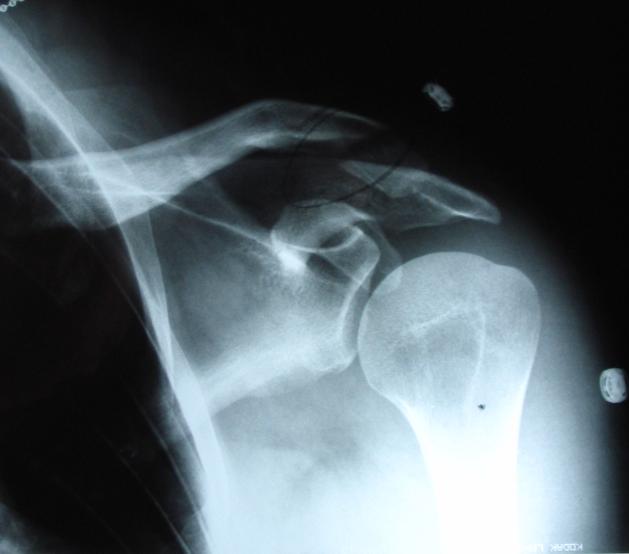

what collerbone? |

the remains of my left collerbone post high side |